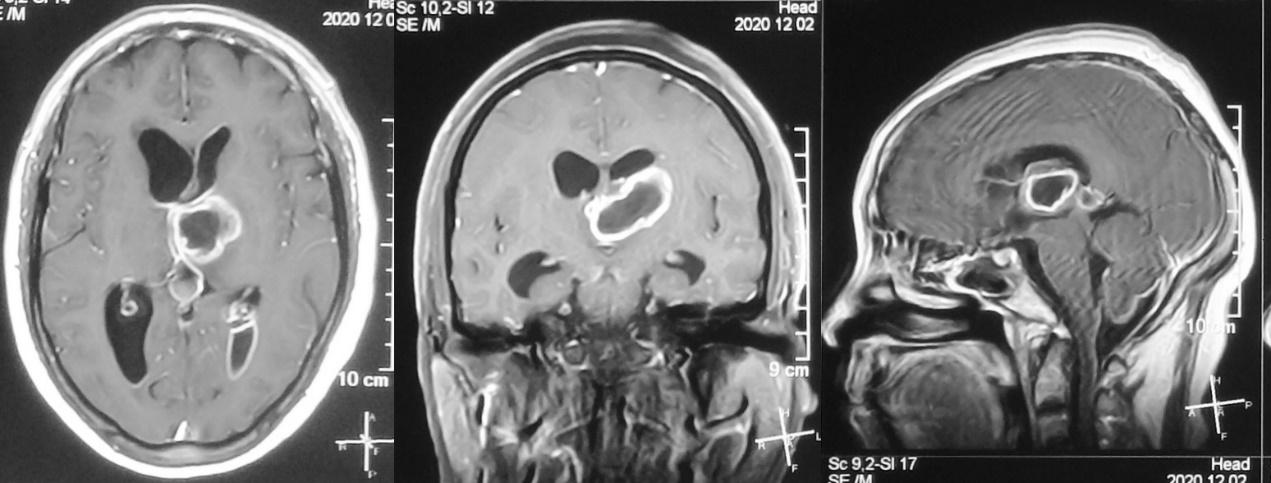

患者病情逐渐加重,出现精神差,饮食差。在当地医生建议下到湖北省武汉市的某三甲医院就诊。于发病后9天即2020年11月17行增强核磁共振检查,发现左丘脑病变明显强化( 图-2 )。当地医生建议手术治疗,但患者担心手术风险较高,于发病后13天即2020年11月21日转到北京某脑科医院。

图-2: 2020年11月17日增强头核磁